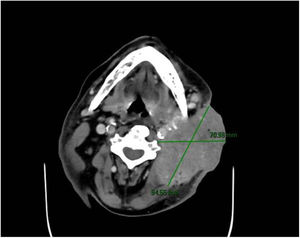

Varón de 64 años, fumador activo que acude a urgencias por presentar una tumoración cervical izquierda junto con fiebre elevada y malestar general de varios días de evolución. A la exploración física: tumoración de 7×4cm con supuración activa y pétrea a la palpación (fig. 1). TAC de tórax y cervical urgente: gran masa de partes blandas, laterocervical izquierda, con densidad heterogénea y burbujas en su interior (fig. 2), invadiendo planos grasos profundos y fistulizando al exterior 8×9cm (fig. 3) compatible con masa maligna abscesificada. Ingreso en la UCI por shock séptico para recibir tratamiento intensivo. Diagnóstico definitivo: neoplasia de la base de la lengua con adenopatía metastásica abscesificada.